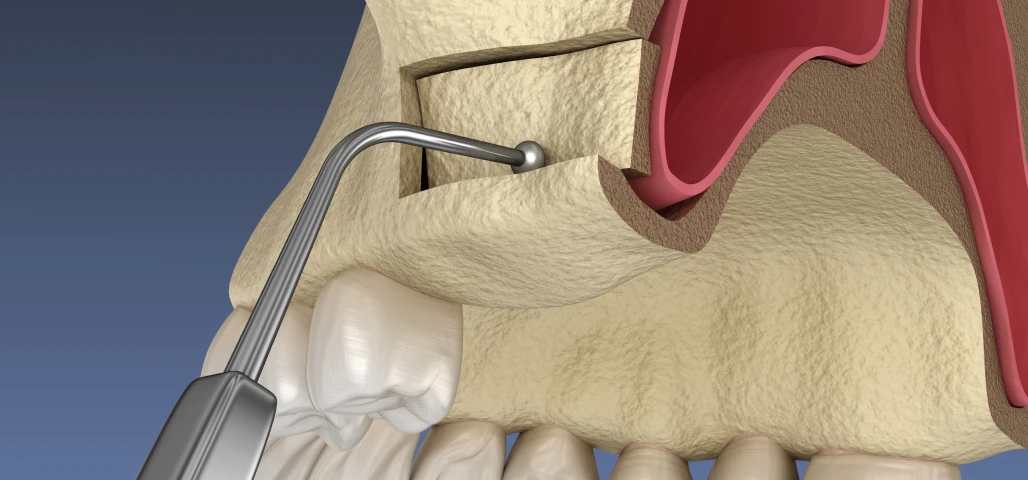

Chirurgie orale

La chirurgie orale regroupe un ensemble d’interventions réalisées au niveau de la bouche, des dents et des mâchoires, allant de l’extraction des dents de sagesse aux actes plus complexes comme les kystes, les freinectomies ou les préparations implantaires.

Au cabinet du Dr Duroux à Cannes, ces actes chirurgicaux sont pratiqués avec rigueur et précision, dans un environnement sécurisé et adapté. L’objectif est d’assurer une prise en charge efficace, en limitant l’inconfort du patient et en favorisant une cicatrisation rapide.